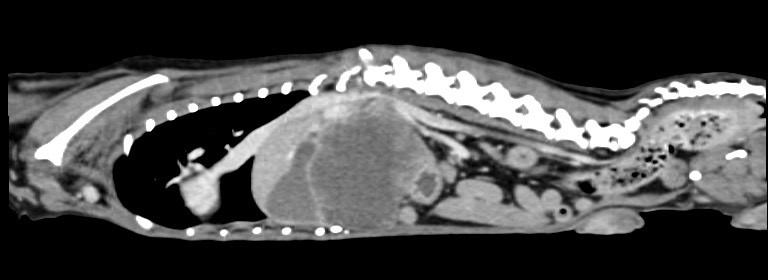

卵巢殘留

卵巢殘留是指雌性動物在進行絕育手術後,仍然有部分卵巢組織殘留,進而導致術後仍然反覆發情,並可能繼發子宮殘端蓄膿、乳腺腫瘤等疾病。而殘存的卵巢,由於體積小且子宮角已被摘除,往往難以找尋。幸而隨著動物醫療進步,依靠電腦斷層、內視鏡等先進設備,卵巢殘留的情況已不再難以處理。

小花是一隻一歲多的母貓,半年前曾在其他醫院做過絕育手術,但手術當下卻只找到單側的子宮卵巢,且在這半年當中仍然反反覆覆地發情,讓飼主十分擔心,於是來到築心尋求治療。在了解小花的狀況後,我們為小花安排了電腦斷層掃描,並在腹腔的左側發現了疑似殘存的卵巢影像(見圖示),接著,在影像定位的協助下順利開腹取出殘存的卵巢和發育異常子宮角,而在殘存的子宮內已然形成了子宮蓄膿。

幸虧子宮蓄膿的情形尚不嚴重,並沒有造成感染範圍的擴散,手術後經過一小段時間的修養,小花目前已經順利拆線,在家過著無憂無慮的生活囉。